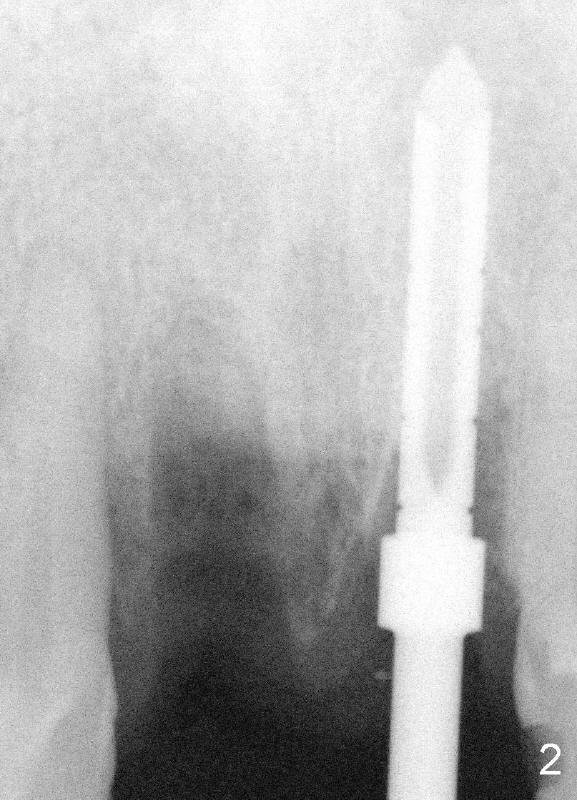

An immediate implant is planned for #9.  Bicon reamers are being used to harvest autogeneous bone from #9 socket during osteotomy (Fig.2). 5x20 mm Tatum tapered implant is inserted with primary stability (Fig.3).  The socket of #8 is debrided, irrigated with copious normal saline and Tetracycline solution, grafted with autogenous bone and Pure Phase Beta-Tricalcium Phosphate and covered by Resorbable Collagen Membrane.